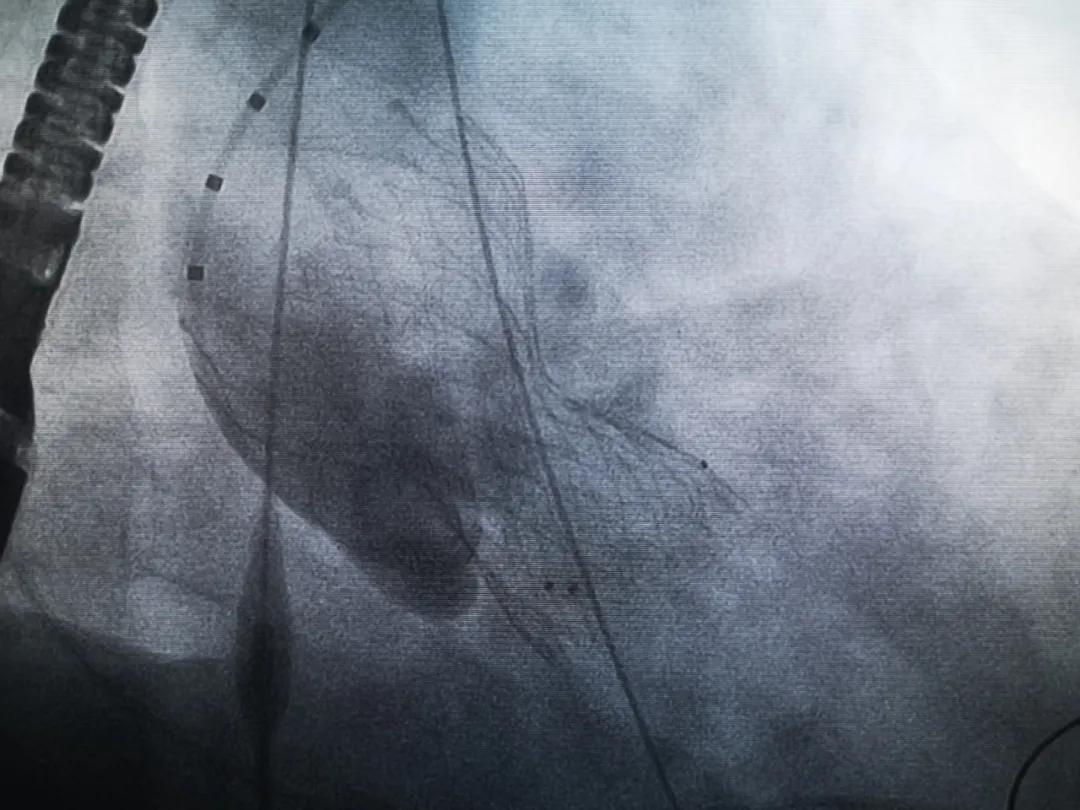

王子的手術(shù)被安排在周五。術(shù)前一天,TAVR團隊再次碰頭討論,從麻醉中血壓控制、球囊擴張、瓣膜釋放,到各種可能突發(fā)狀況的應(yīng)對,都提前制定了方案。尤其是瓣膜鈣化極為嚴(yán)重,對于擴張球囊型號的選擇、擴張的力度以及瓣膜植入后瓣周漏的發(fā)生預(yù)測,都具有很大挑戰(zhàn)。然而,如果沒有這些挑戰(zhàn),他又何必選擇我們呢!

手術(shù)過程緊張而有序,心臟沒有停跳,也沒有太大的血壓波動;球囊擴張的恰到好處,瓣膜釋放之后超聲醫(yī)生的評估是至關(guān)重要的,因為我們提前就準(zhǔn)備了后擴張,也準(zhǔn)備了瓣中瓣,甚至還準(zhǔn)備了瓣周漏封堵。所幸的是,超聲診療中心劉夢梅醫(yī)生說:沒有返流、沒有瓣周漏,瓣膜形態(tài)良好,跨瓣壓差約17mmHg(相較于術(shù)前的87mmHg還是可以接受的)。瓣膜置入的成功并不是慶祝的時候,從戰(zhàn)場撤退仍然需要謹(jǐn)慎。由于王子特別胖,腹股溝區(qū)脂肪尤為肥厚,在股動脈插管拔除、確認搏動正常之后,便逐層縫合。同時為了美觀、縫合之后不至于鼓個包出來,我們又仔細剪除了部分脂肪。術(shù)后次日,王子便可以下床活動了。